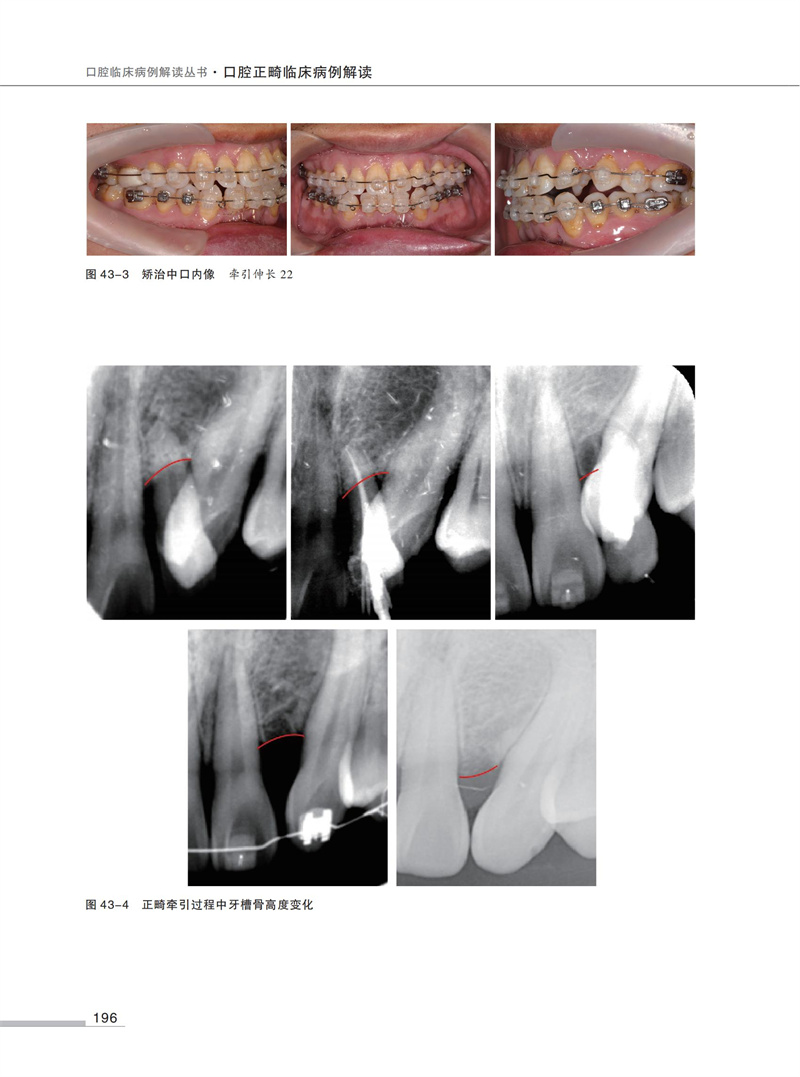

【口腔正畸臨床病例解讀】

54例正畸經典病例,每例病例均包含檢查、模型分析、診斷、治療計畫、弓絲序列、矯治結果及矯治體會等基礎資訊。

全書共分為7部分54例病例,每部分依次討論安氏I類錯? 矯治、安氏II類錯? 矯治、安氏III類錯? 矯治、正畸-正頜矯治嚴重骨型錯? 畸形、多學科聯合矯治複雜錯? 畸形、舌側矯治、隱形矯治。 在病例的選擇中兼顧高角、低角患者,骨性、牙性問題,手術優先、普通順序的手術治療,力求盡可能全面地展示臨床上常見的病例種類和治療方法。 本書精選病例,討論全面,完整地展示出從診斷分析到治療實踐的臨床思維全過程。